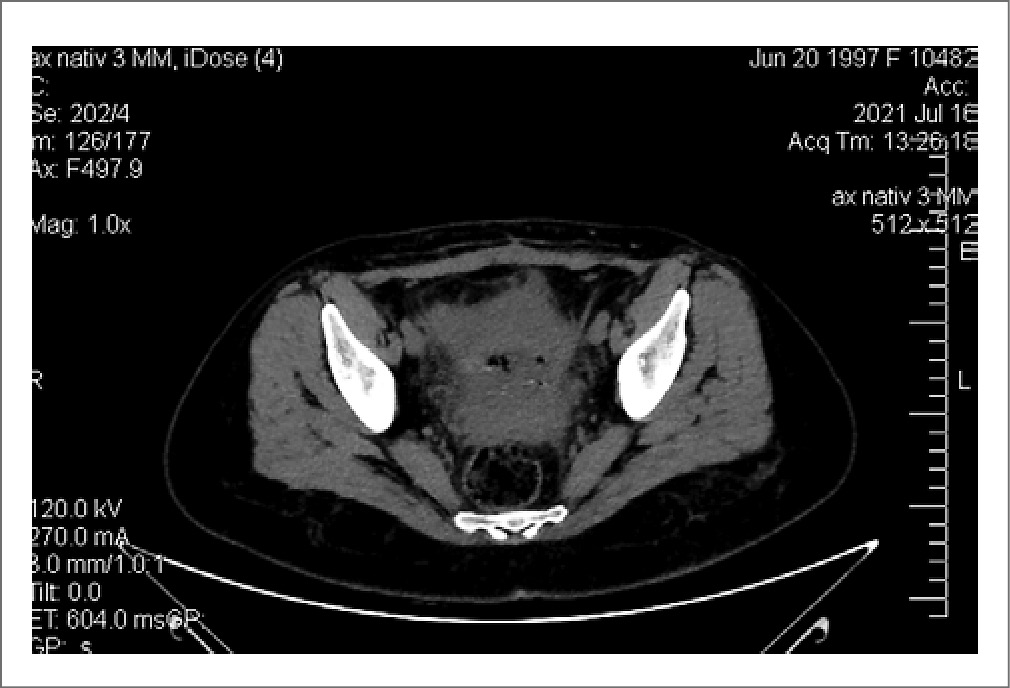

По данным ультразвукового исследования органов брюшной полости и забрюшинного пространства патологических изменений не выявлено. Компьютерная томография органов брюшной полости и малого таза (рис. 3) показала, что матка незначительно увеличена в размере, по латеральному краю справа от тела матки отмечалось небольшое скопление свободной жидкости.

Рис. 3. Компьютерная томография органов малого таза (небольшое скопление свободной жидкости справа от матки).